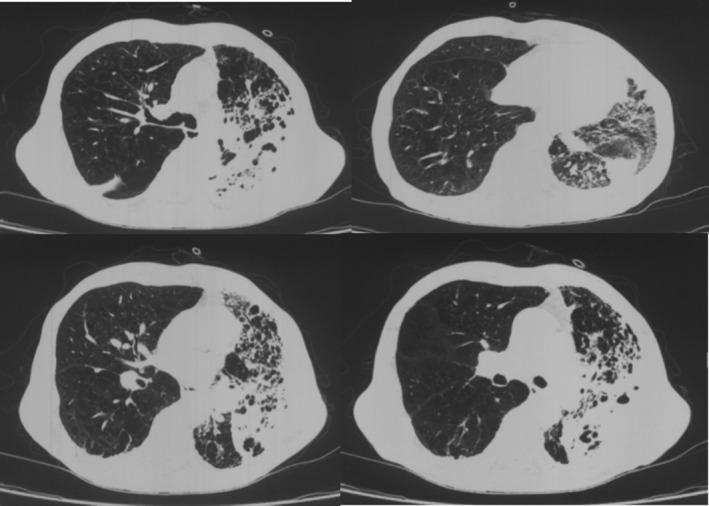

is a major pathogen in hospital-acquired infections notorious for its strong acquired resistance and complex drug resistance mechanisms. Owing to the lack of effective drugs, the mortality rate of extensively drug-resistant pneumonia can reach as high as 65%. This article analyzes a case where a combination of cefoperazone-sulbactam, polymyxin B, and minocycline with rifampicin successfully treated XDR-AB pulmonary infection. Combination therapy is effective and has a particular clinical value.

是医院获得性感染中的主要病原体,以其强大的获得性耐药性和复杂的耐药机制而臭名昭著。由于缺乏有效的药物,广泛耐药性肺炎的死亡率可高达65%。本文分析了一例头孢哌酮-舒巴坦、多粘菌素B、米诺环素联合利福平成功治疗XDR-AB肺部感染的病例。联合治疗有效,具有特殊的临床价值。